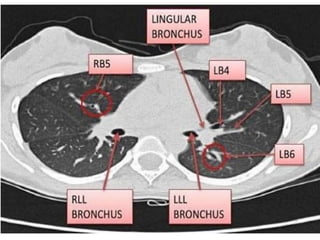

CAÂY PHEÁ QUAÛN VAØ PHAÂN THUØY PHOÅI

+CT cho chi tieát giaûi phaãu toát raát nhieàu so vôùi X

quang qui öôùc

+Phaân tích hình aûnh CT

-Caây pheá quaûn

-Phaân thuøy phoåi

-Raõnh maøng phoåi